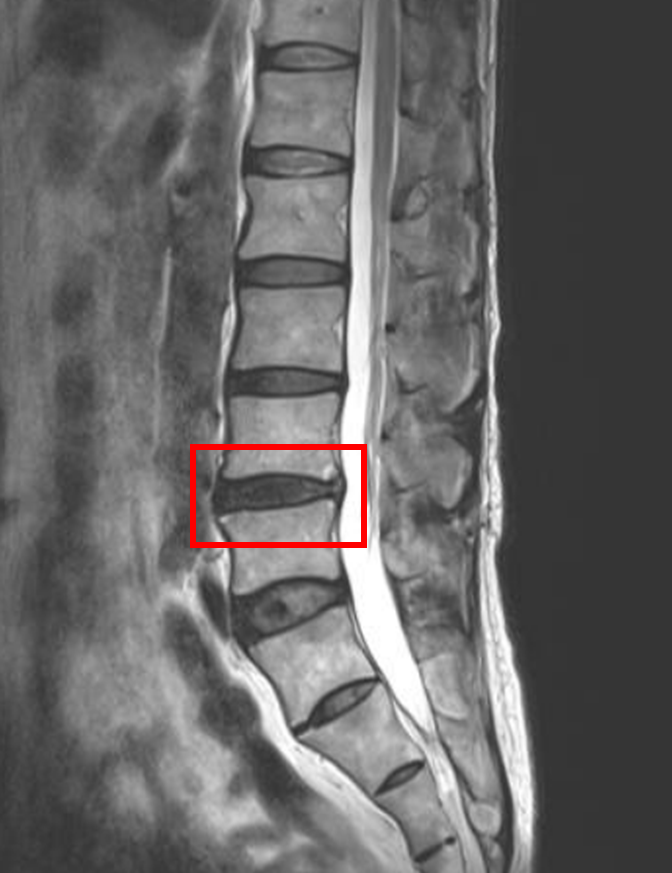

この患者様は赤い枠で示されている箇所(L4/5)に椎間板変性を認めます。

今回の患者様は、椎間板変性が原因の患者様でした。